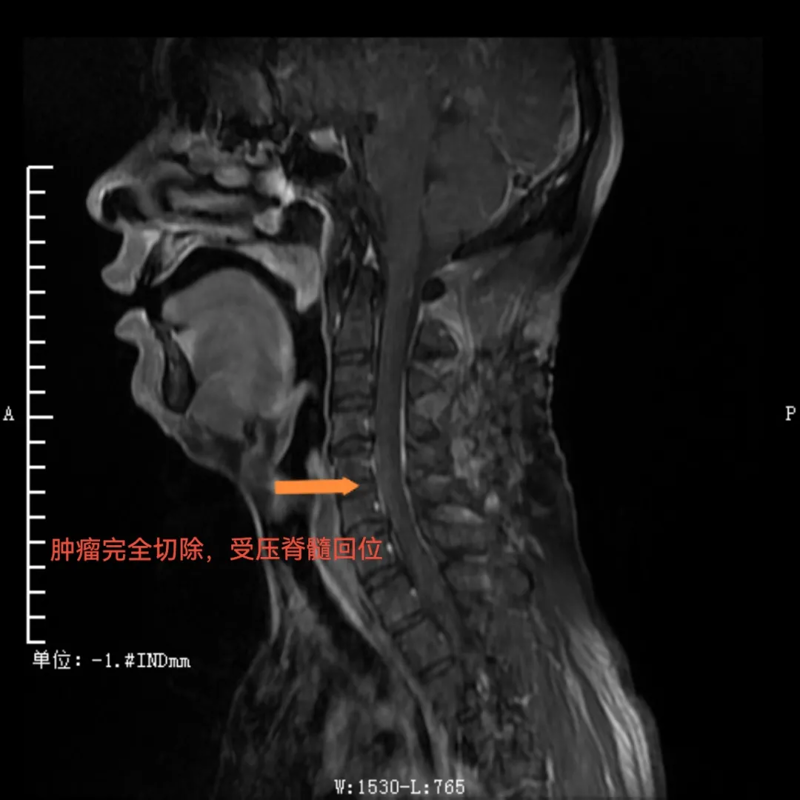

术后,肿瘤完全切除,受压脊髓回位

与传统手术需要完全切除肿瘤节段全椎板不同,这种新的手术方式术后仅需将掀起的椎板纳还并以丝线固定即可,无需使用金属连接耗材固定。这不仅使得复位效果更佳,而且患者在术后复查CT、磁共振时无金属伪影干扰,让检查结果诊断更准确,还为患者节省了相当大的一笔费用。